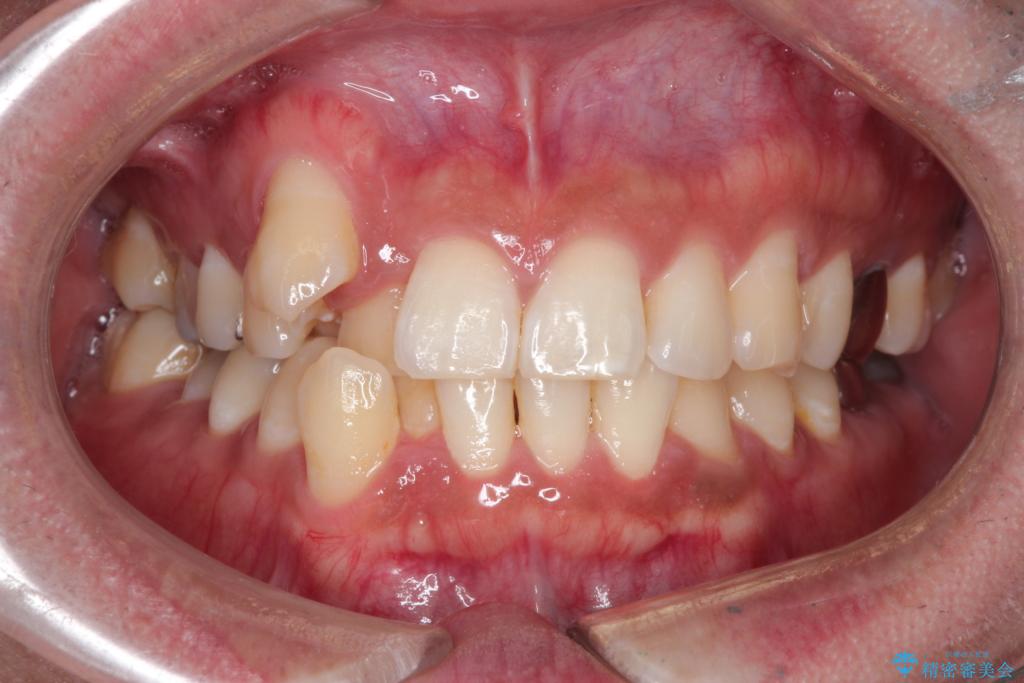

【ワイヤー矯正】八重歯と下の歯の凸凹を治したい

- 主訴:右上の八重歯と、下の歯の凸凹を治したい

右側2級、左側1関係だったため、右側上下第一小臼歯を抜歯し、ワイヤー矯正を行いました。

期間:2年6カ月